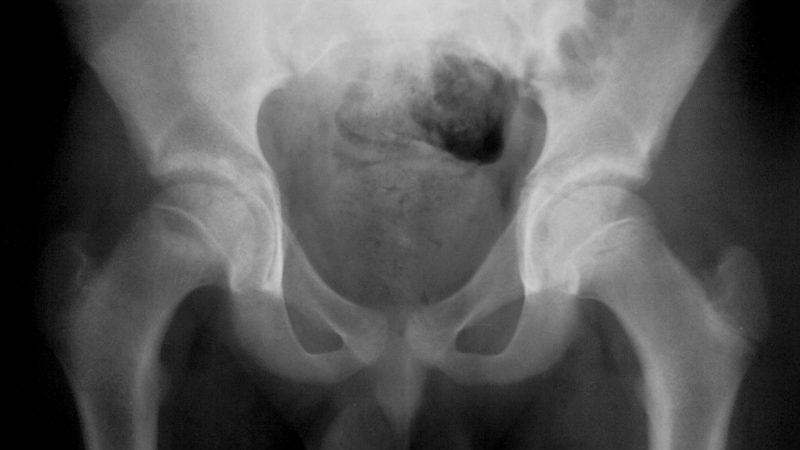

Фото рака тазобедренного сустава:

- Рентгенография. Этот метод позволяет просветить костную структуру. Результаты помогут оценить развитие патологических изменений и общее состояние сустава.